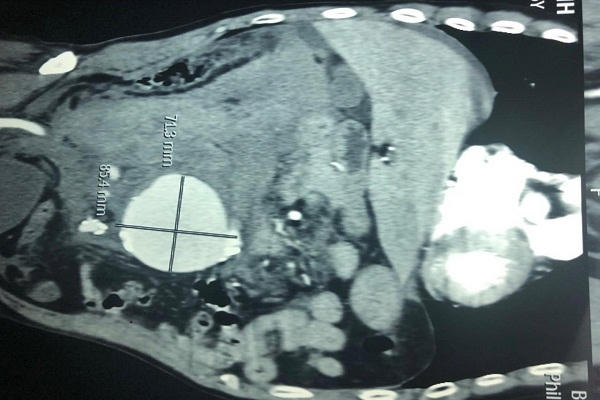

Bác sĩ Hồ Khánh Đức- Khoa Phẫu thuật Tim-Mạch máu Bệnh viện Bình dân cho biết, bệnh nhân chuyển đến trong tình trạng rất nguy kịch, sốc mất máu, tụt huyết áp, tri giác lơ mơ, tiếp xúc chậm. Các bác sĩ xác định bệnh nhân vỡ túi phình động mạch chủ bụng đường kính 71mm và chuyển ngay vào phòng mổ cấp cứu.

Theo bác sĩ Đức, phình động mạch chủ bụng là tình trạng động mạch bị giãn ra to hơn bình thường, thành mạch dần yếu, mỏng, có nguy cơ vỡ đột ngột dưới áp lực máu. Đây là động mạch lớn nhất trong cơ thể dẫn máu từ tim đến các cơ quan và các mô ở nửa phần dưới của cơ thể. Vỡ túi phình có thể làm người bệnh tử vong bất cứ lúc nào. Phần lớn các trường hợp phình động mạch chủ bụng không có biểu hiện về mặt lâm sàng. Khi phát hiện bệnh, người bệnh sẽ được chụp phim CT scan mạch máu để đánh giá hình thái và kích thước túi phình và được các bác sĩ chuyên khoa phẫu thuật mạch máu theo dõi, phẫu thuật khi túi phình có kích thước lớn.